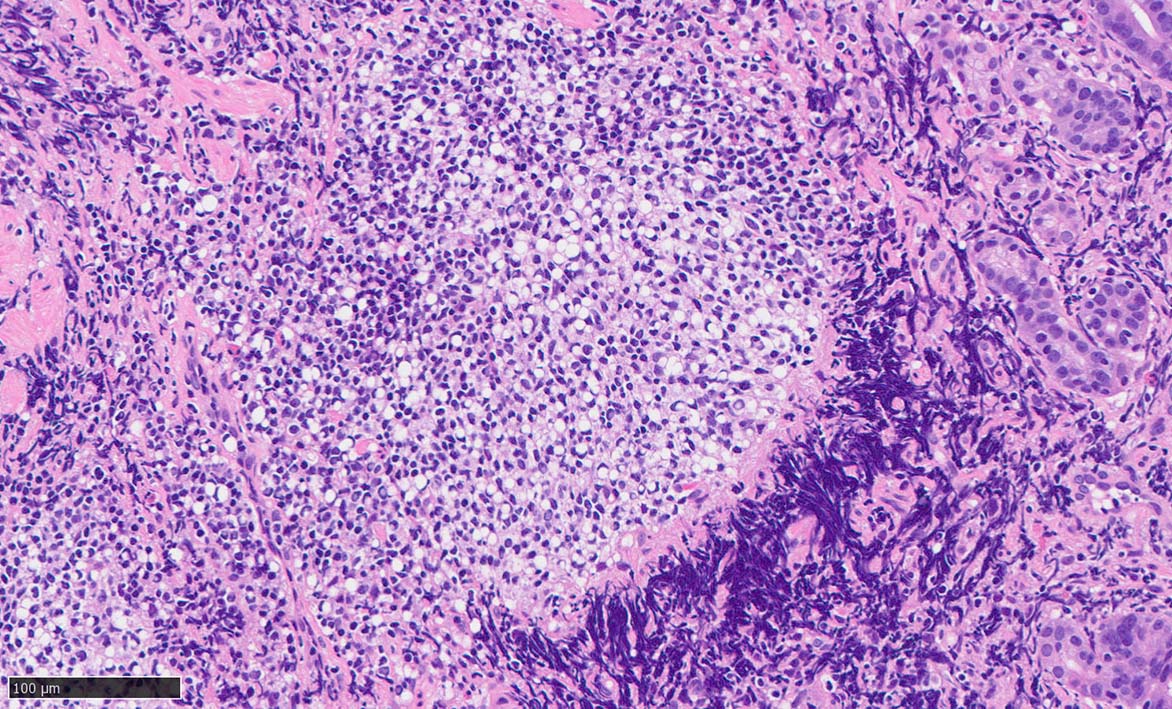

Signet-ring cell lymphoma of the stomach

40歳代後半 男性. 胃生検組織

stomach biopsy, HE

x200

非結節部位